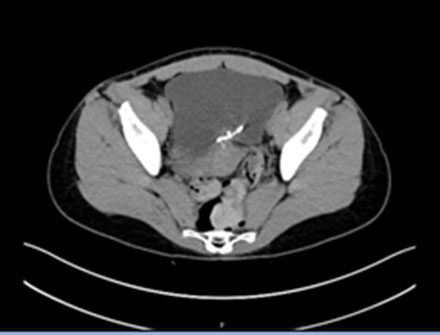

A migration diagnosis can be reached through ultrasound and plain film [7]. In our case, the diagnosis was confirmed through a cystoscopy performed by an outpatient urologist. To investigate further, we decided to perform a CT scan to ensure the extension and location of the IUD (Figure 2 and Figure 3).

Figure 3: A transverse section of the patient’s abdominal CT scan reveals the dislocated IUD through the posterior wall of the bladder.